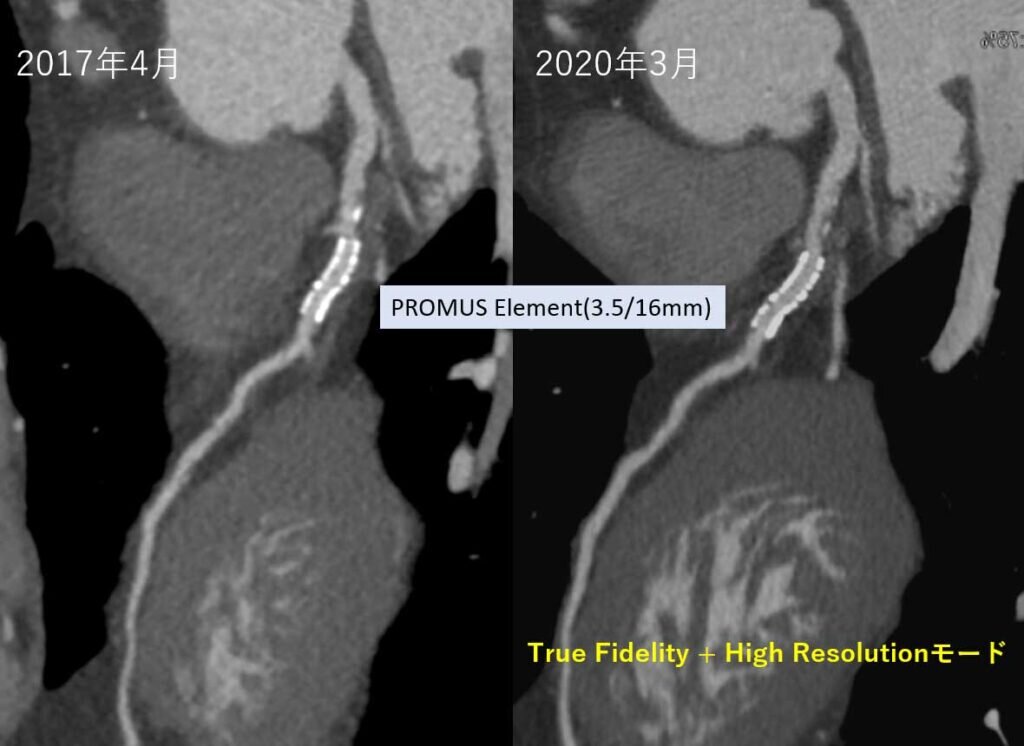

更に、ディープラーニングを用いて開発された次世代画像再構成法TrueFidelity™ Imagingが搭載され、従来より30~50%被ばくを減らしても従来と同等もしくはそれ以上の画質が提供できます。この再構成法と「High Resolutionモード」との併用で冠動脈内に留置されたステント内部が、従来より詳細に描出することも可能です。

当院では日々研鑽して、負担が少なく、より高画質な画像を提供できるよう撮影法を検討し続けています。